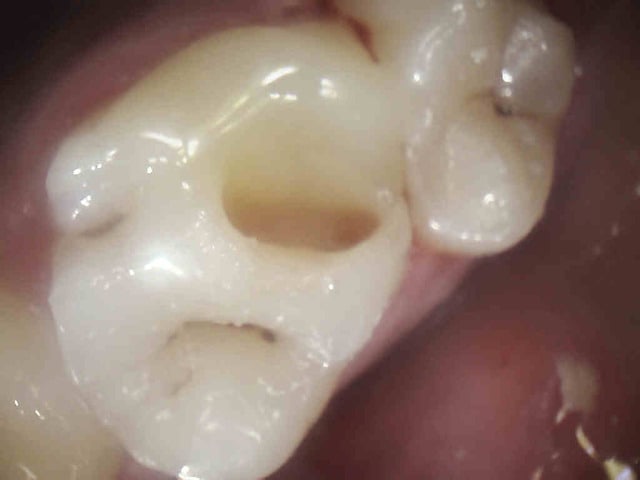

C'est quoi la proba d'avoir une deuxième bio à 5 canaux en 2 semaines?

(la radio excentrée est dégueulasse, mais ça montre les doubles courbures, quelques peu minimisées par l'angulateur...